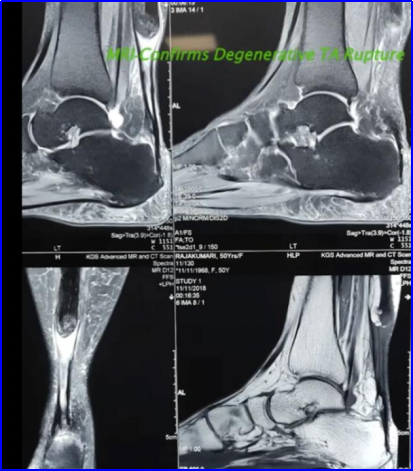

MRI:能清晰显示肌腱断端的萎缩、回缩程度以及缺损间隙(Gap)的大小,这对于制定手术方案至关重要。

图 3 磁共振成像(MRI)证实跟腱(TA)退行性撕裂并伴近端回缩移位。